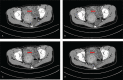

Patient concerns: A 54-year-old woman presented with a one-year history of recurrent episodes of hypogastric pain, with vomiting, nausea, melena, and weight loss of 10 kg in recent 5 months.

Lessons: This report showed a rare case of diffuse IGNM not associated with NF1 or MEN2b. Preoperative radiological examination suggested an intestinal GIST, yet the final diagnosis of diffuse IGNM was made according to the pathological examination of the resected specimen. Although the prevalence of ganglioneuromatosis is low, this condition should be considered in the differential diagnosis of intestinal mass in adults.